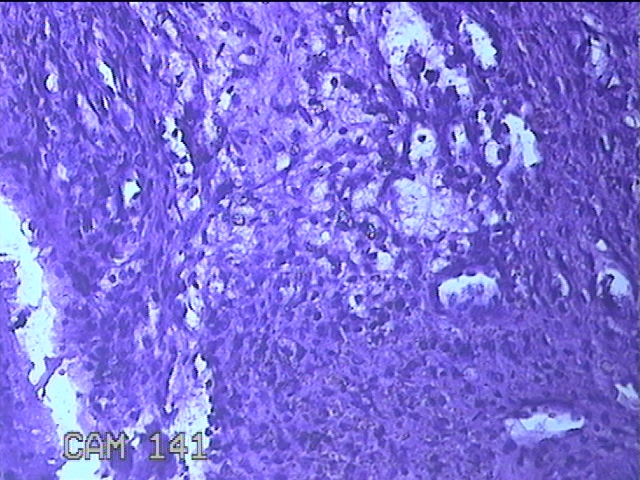

右下唇肿物

性别

女

年龄

12岁

临床诊断

唇囊肿

一般病史

右下唇部肿物一月余。

标本名称

大体所见

灰白粉红色肿物0.8x0.7x0.2cm一个,表面光滑。

图4